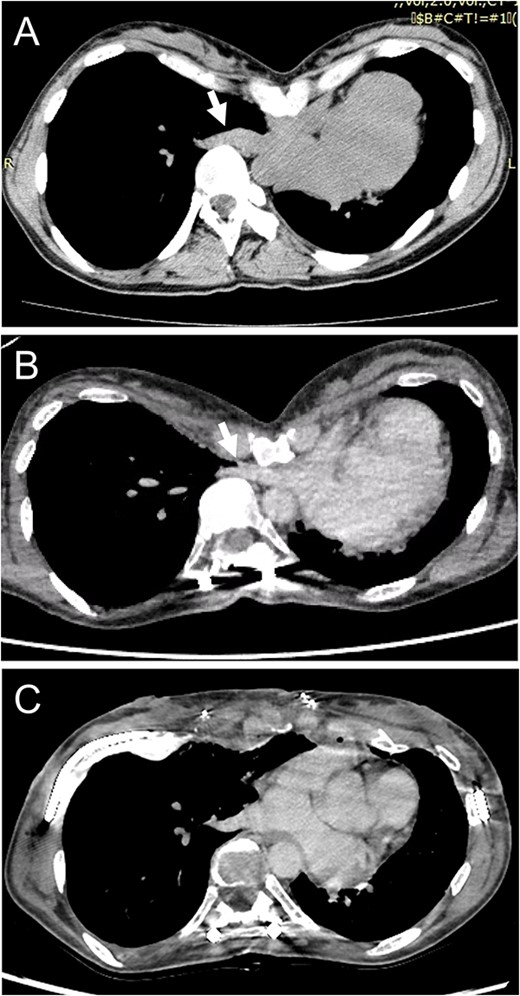

(A) Chest CT shows no compression of the right inferior pulmonary vein (IPV) before scoliosis repair (arrow). (B) Severe right IPV stenosis is induced by posterior spinal fusion (arrow). (C) Postoperative chest CT indicates that right IPV stenosis is released by elevation of the depressed sternum.

A spirometry test before surgery showed a vital capacity (VC) of 2.0 L (76% of predicted). After surgical repair of her scoliosis, VC was 1.7 L (66% of predicted) and she experienced ventilatory impairment. As part of the imaging test, a chest X-ray demonstrated thoracic scoliosis with a Cobb angle of 62° before surgery, and the curve improved due to a posterior correction of the scoliosis. On the other hand, chest computed tomography (CT) revealed that severe chest excavation presented a lower sternum as an extreme point, and the depressed sternum compressed cardiovascular structures. Notably, a preoperative chest CT indicated that there was no compression of the right inferior pulmonary vein (IPV) (Fig. 1A); however, after scoliosis surgery, severe right IPV stenosis occurred secondary to narrowing of the space between the 9th thoracic vertebrae, which were shifted toward the midline following posterior spinal fusion and lower sternal depression as a result of PE (Fig. 1B). An echocardiogram showed that the systolic right inferior pulmonary venous flow (PVF) increased from 42.5 cm/s to 135 cm/s during changing position.

According to these imaging results, exacerbation of dyspnea was attributed to a ventilation-perfusion mismatch because of severe right IPV stenosis. We planned to perform surgery for PE repair to achieve surgical release of the IPV stenosis. The patient underwent a Combined Ravitch and Nuss (CRN) procedure. Thoracoscopy revealed IPV distention due to compression by the severely depressed sternum. The sternal depression was corrected with separation of the 4th–7th costal cartilages, followed by sternal elevation using two pectus bars. She was discharged on the 11th postoperative day without any complications. A postoperative chest CT exhibited an improvement of sternal depression and the right IPV stenosis (Fig. 1C). An echocardiogram revealed that the systolic PVF changed from 49.7 cm/s to 75.7 cm/s during postural changes, and the increase in PVF was mitigated, so that her shortness of breath was relieved postoperatively.